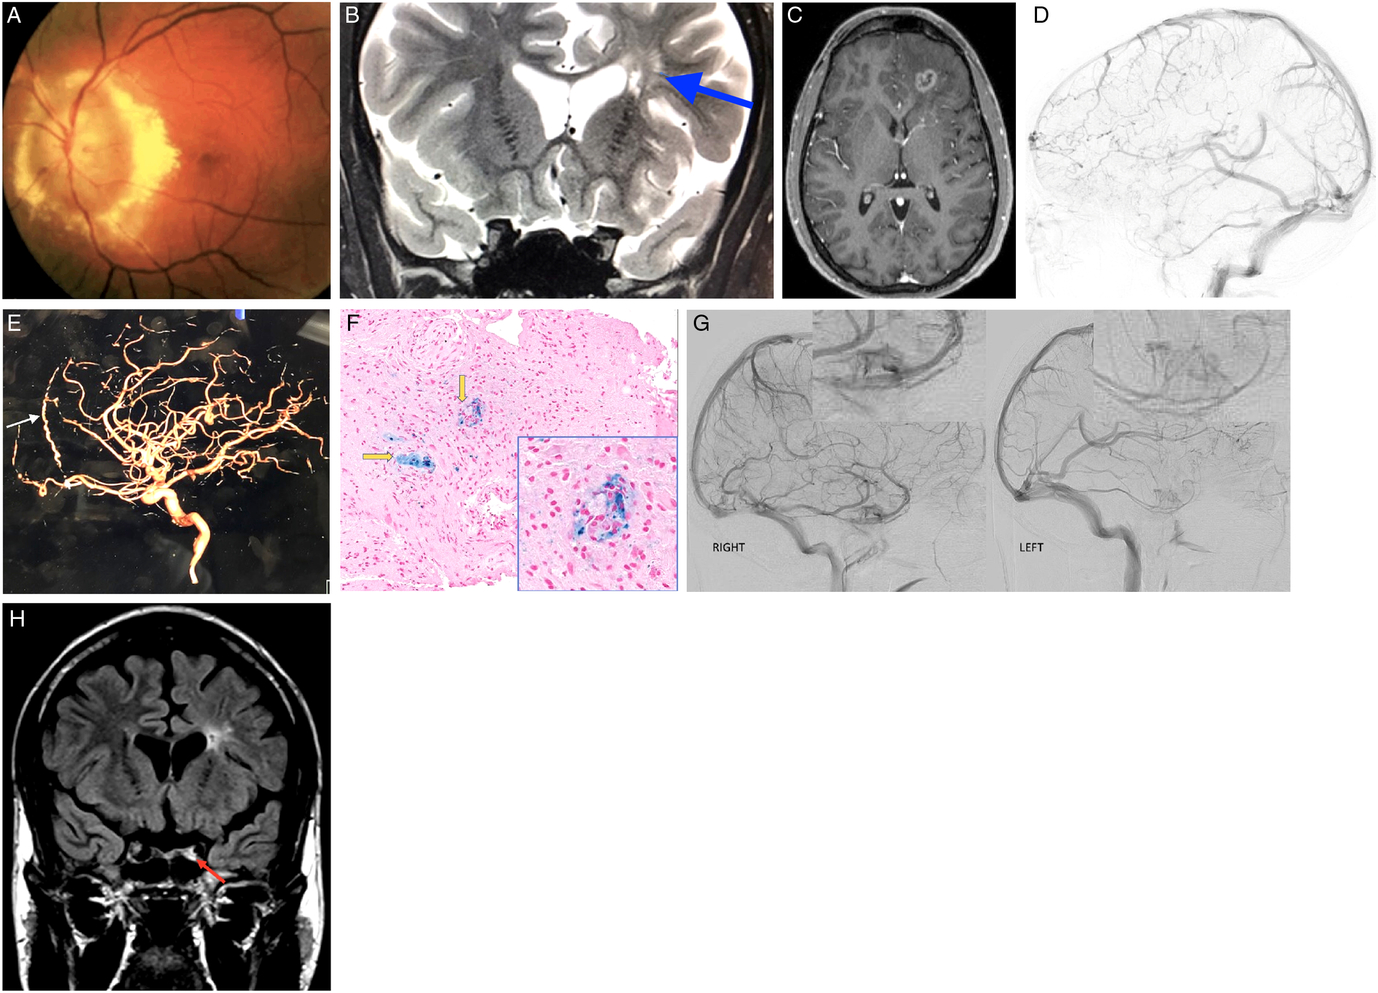

Figure 1: (A) Fundus photo of the left eye demonstrating massive optic nerve head swelling with surrounding hard exudates. (B) MRI. Corontal T2 sequence demonstrating hyperintense lesions deep in the left frontal lobe (blue arrow). (C) MRI. Axial T1 with gadolinium demonstrating left frontal mass lesion with peripheral enhancement. (D) Left lateral internal carotid angiogram demonstrating "pseudophlebitic pattern" in the left frontal lobe. (E) Left lateral internal carotid angiogram demonstrating enlarged left anterior falcine artery (white arrow). (F) Frontal lobe biopsy specimen. Hematoxylin and eosin (H&E) and Prussian blue stain demonstrating perivascular macrophages (yellow arrows). (G) Right and left lateral carotid angiograms demonstrating decreased left cavernous perfusion. (H) MRI. Coronal FLAIR demonstrating left hyperintense signal in the left cavernous sinus corresponding to cavernous sinus thrombosis.

Two and a half years after the initial presentation, the patient developed a generalized seizure. MRI of the brain was urgently performed and demonstrated a left frontal lobe mass with surrounding edema and peripheral enhancement (Figure 1C). Brain biopsy was performed and demonstrated macrophages surrounding blood vessels and unexpected areas of necrosis but was deemed indeterminate. Second opinion on the results of the biopsy reported findings inconsistent with both demyelination and arterial infarct. Cerebral angiography was performed and demonstrated unusual left hemispheric cortical veins without arteriovenous shunting. After consulting with pulmonary, rheumatological, and neuroradiological services, neurosarcoidosis was felt to be a unifying diagnosis. After receiving 3 days of 1 g of intravenous methylprednisolone, treatment with oral mycophenolate mofetil commenced. MRI of the brain performed 2 months later demonstrated dramatic resolution of left frontal lobe lesion.

While satisfied with radiological improvement, the case was reexamined and the diagnosis of neurosarcoidosis was challenged. Cerebral angiogram was meticulously reexamined. Unusual tortuous cortical veins in the left hemisphere were noticed and felt to be compatible with “pseudophlebitic” pattern seen in brain dural arteriovenous fistulas (bdAVF) (Figure 1D).Reference Geibprasert, Pongpech, Jiarakongmun, Shroff, Armstrong and Krings1 Enlarged left anterior falcine artery was also demonstrated (Figure 1E). Review of the literature on the pathological findings seen in bdAVFs yielded one published retrospective study of spinal dural AVFs biopsies that were performed because the lesion resembled a neoplasm radiologically. Their reported tissue findings were the presence of thick-hyalinized vessels in all cases, hemosiderin-laden macrophages in 71%, and necrosis in 29%.Reference Rodriguez, Crum, Krauss, Scheithauer and Giannini2 Third review of brain biopsy was thus requested and reported the presence of thick-hyalinized vessels, hemosiderin-laden macrophages, and areas of necrosis in our case that were all compatible with chronic venous congestion (Figure 1F).

A decision was made to perform a second cerebral angiogram as the presence of previously not identified bdAVF was felt to be the most likely diagnosis; however, it also failed to demonstrate it.Reference Geibprasert, Pongpech, Jiarakongmun, Shroff, Armstrong and Krings1 Detailed review of both angiographies was undertaken and revealed unusual tortuous cortical veins in the left frontal lobe consistent with “pseudophlebitic” pattern seen in bdAVFs.Reference Geibprasert, Pongpech, Jiarakongmun, Shroff, Armstrong and Krings1 It was previously reported that in small number of patients bdAVFs can spontaneously close off during an acute venous hypertensive event and thus cannot be demonstrated on follow-up cerebral angiograms.Reference Kim, terBrugge, Krings, Willinsky and Wallace3 We believe that this is what happened in our patient, and spontaneous closure of his bdAVF explained the resolution of the left frontal mass lesion on follow-up MRI after brain edema has resorbed. It was also noticed that there was definite decreased perfusion of the left cavernous sinus on both angiographies (Figure 1G). When all imaging was reexamined, subtle left cavernous sinus thrombosis (CST) was seen in all previous studies (Figure 1H). Full hypercoagulability workup revealed significantly elevated titers of anticardiolipin IgG antibodies (46 CU, normal <20), which were even higher on repeat testing performed 1 month later. Hypercoagulable state due to anticardiolipin antibody syndrome was felt to be the most likely cause of long-standing left CST. Treatment with oral steroids was discontinued; and at the last follow-up 4 years after presentation, visual acuity was hand motions in the affected eye with the atrophic-looking optic nerve. There were no new brain lesions on follow-up neuroimaging.